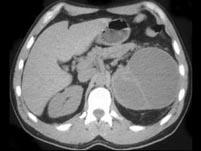

问题 女,48岁,左腰部胀痛不适2个月余,请根据所示图像,选择最可能诊断 ( )

选项 A、左侧肾脓肿 B、左侧肾积水 C、左侧肾囊肿 D、左侧多囊肾 E、左侧囊性肾癌

答案 E